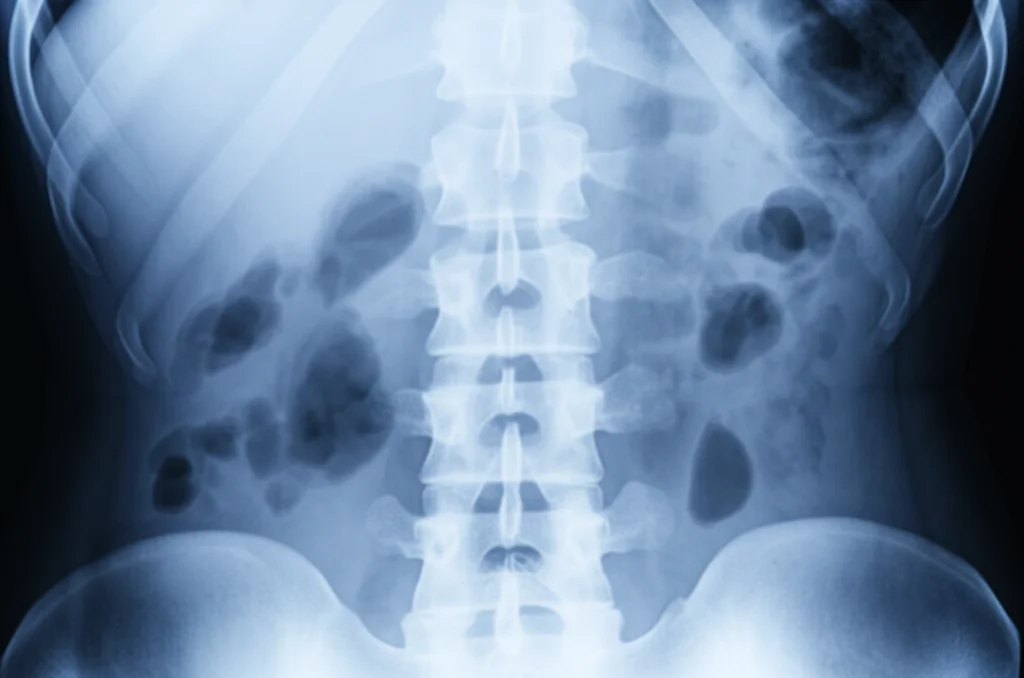

Ciao a tutti! Oggi voglio parlarvi di un argomento che tocca da vicino molti adulti: la deformità spinale adulta (ASD). Si tratta di un problema complesso della colonna vertebrale che può presentarsi in tanti modi diversi e, diciamocelo, può davvero impattare sulla qualità della vita. Negli ultimi anni, grazie ai progressi nella biomeccanica, nell’anatomia e nelle tecnologie di imaging, ne sappiamo molto di più. È chiaro che queste deformità non riguardano solo come appare la nostra schiena (sui piani coronale, sagittale e assiale), ma influenzano pesantemente come ci sentiamo e come viviamo nel lungo termine, quelli che i medici chiamano patient-reported outcomes (PROs), ovvero i risultati percepiti direttamente da noi pazienti.

I ricercatori hanno analizzato retrospettivamente i dati di pazienti operati per ASD tra il 2018 e il 2022. Hanno incluso persone che avevano fallito almeno sei mesi di trattamento conservativo e presentavano criteri radiografici specifici (come un certo grado di disallineamento tra bacino e lordosi lombare, inclinazione pelvica, ecc.). Hanno escluso i più giovani, chi aveva già subito interventi alla colonna o chi aveva deformità causate da tumori, infezioni, traumi o condizioni neuromuscolari.